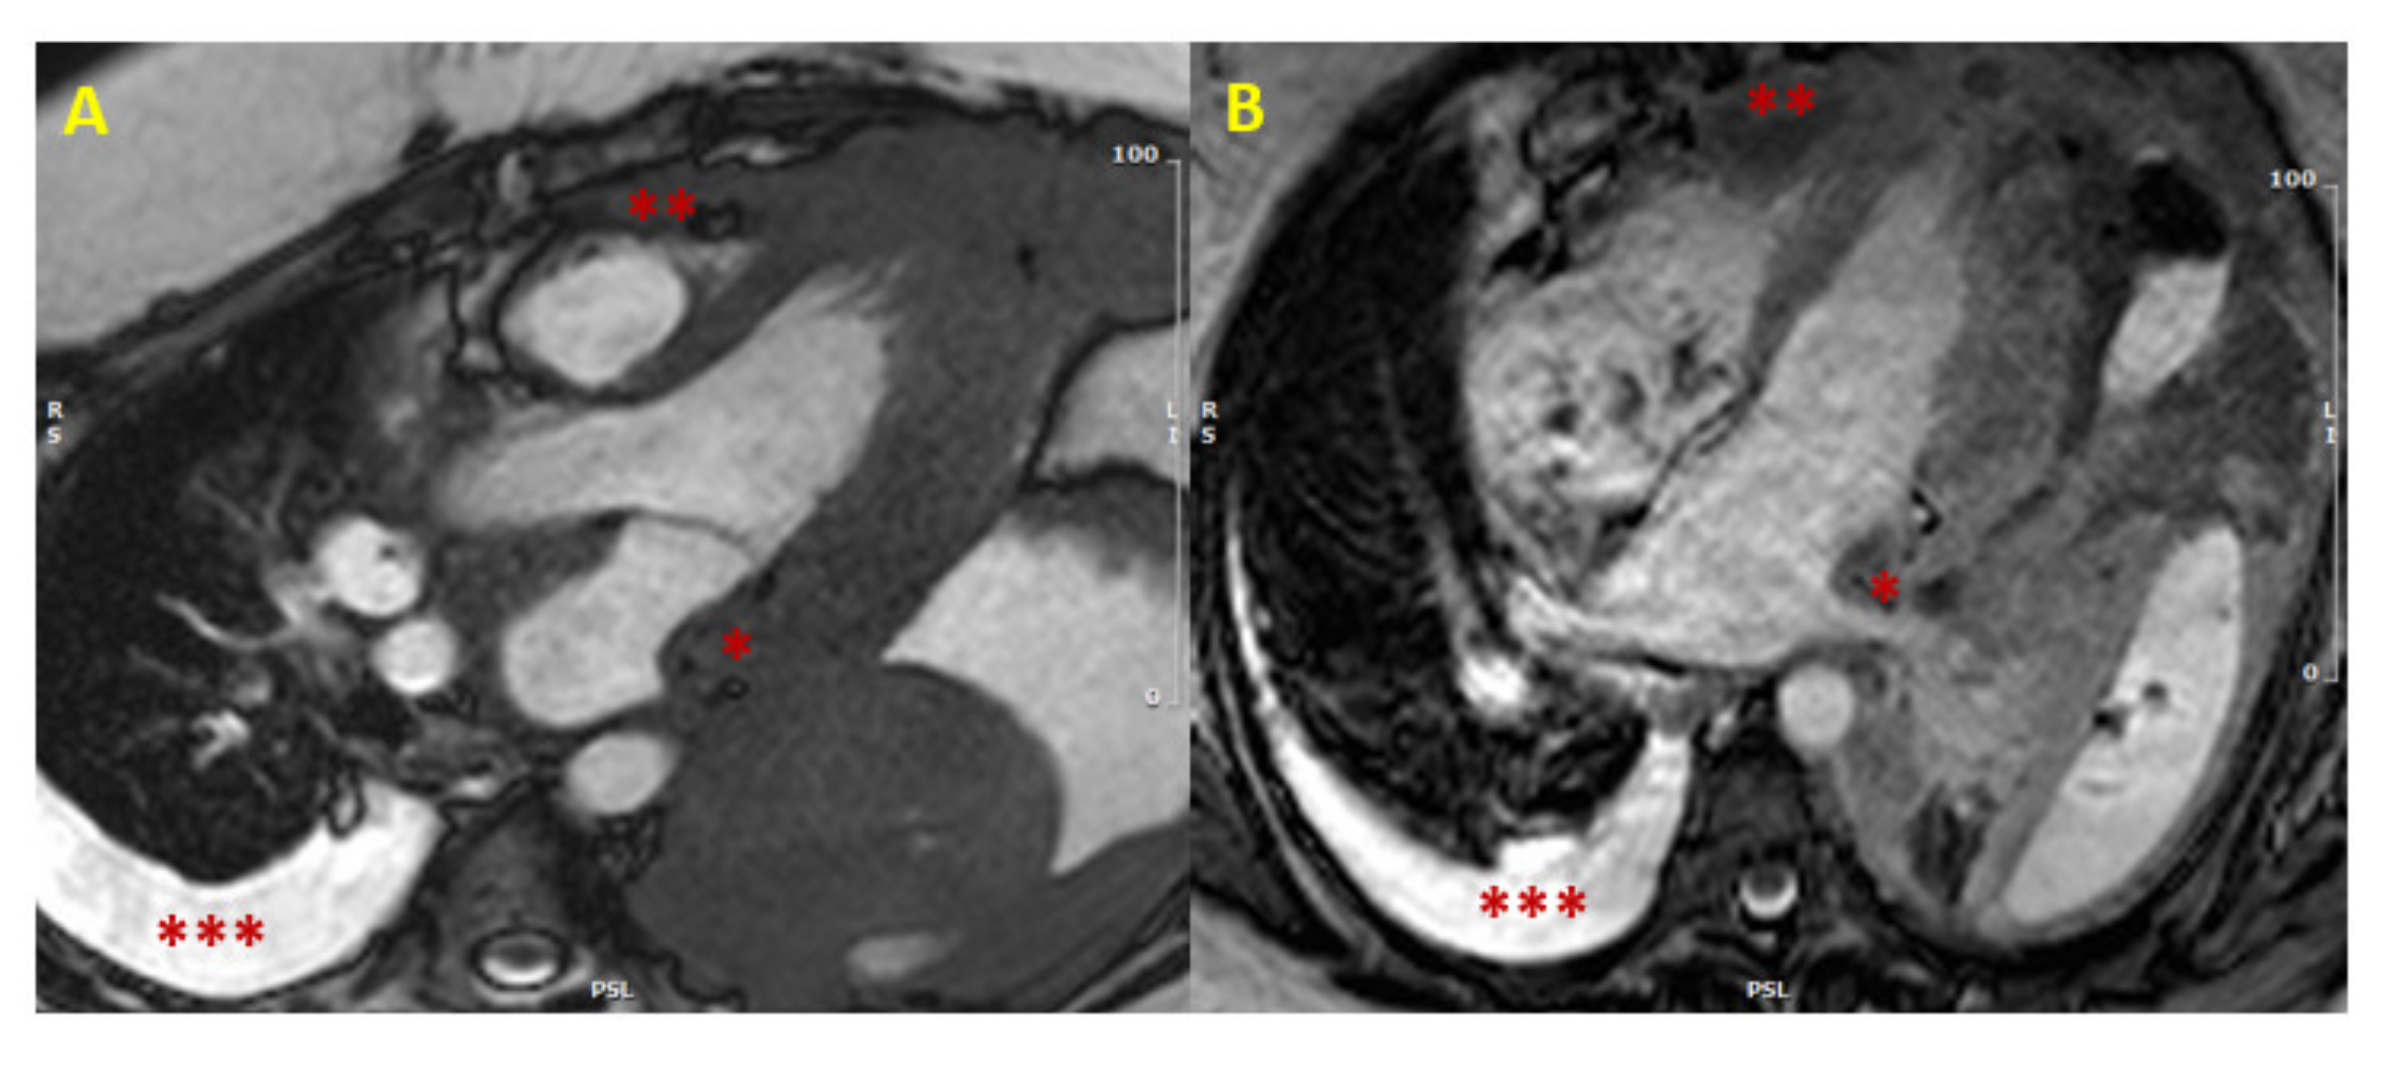

Figure 1.

Cardiac lymphoma at CMR. SSFP images in long axis (3-chamber view in Panel (A), and 4-chamber view in Panel (B)) showing concomitant hypertrophy of left atrial wall (single asterisk *) and RV (two asterisks **). The presence of multiple areas of hypertrophy and pleural effusion (three asterisks ***) are “red flags” for malignancy. (CMR = cardiac magnetic resonance; SSFP = steady-state free precession; LV = left ventricle; RV = right ventricle).

In case of hypertrophy of the interventricular septum at echocardiography, some features may be considered as red flags: among these are a concomitant thickening of the right ventricle, of the atrial walls or of the interatrial septum, and pericardial and/or pleural effusion, because they imply a higher probability of malignancy, and make the diagnosis of a common HCM less likely (Figure 1). Representative of this is the case reported by Kuchynka et al. of a 38-year-old male, with a month-long history of abdominal lymphadenopathy, whose echocardiographic imaging at workup gave grounds for suspicion of HCM [29]. Upon renewed ultrasound investigation, the thickening of the interventricular septum was confirmed, but also a thickening of the right ventricle’s free wall and of the interatrial septum, with a large pericardial effusion, became evident. The ensuing CMR showed diffuse heterogenous late gadolinium enhancement (LGE) in the thickened segments of the myocardium, highly suggestive of a lymphoproliferative disease. Eventually, histological analysis of an enlarged lymph node confirmed the diagnosis of non-Hodgkin lymphoma. After chemotherapy, complete remission was achieved, with normalization of ventricular wall thickness and resorption of the pericardial effusion.